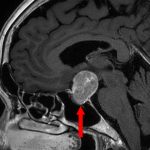

'24年10月

50代

頭蓋咽頭腫

頭蓋内腫瘍摘出術

No.’24_84 手術前1

No.’24_84 手術前2

No.’24_84 摘出 前

No.’24_84  摘出 中

No.’24_84 摘出 後